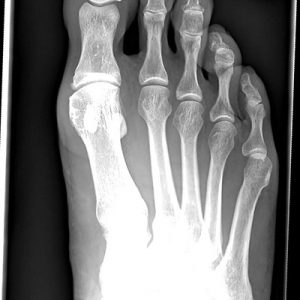

Schneiderballen – verdickter Kleinzehballen

Ähnlich wie an der Großzehe, kann es auch an der kleinen Zehe Fehlstellungen geben, wenn der entsprechende 5. Mittelfußstrahl zu weit abgespreizt ist. Es bildet sich eine schmerzhafte Schwiele am Köpfchen des 5. Mittelfußknochens, welche im Schuh drückt.

Je nachdem, wie stark die Fehlstellung ausgeprägt ist, kann es notwendig werden, den Knochen am Köpfchen abzutragen oder den Knochen im Köpfchenbereich beziehungsweise im Schaftbereich umzustellen (das 5. Mittelfußköpfchen wird dadurch wieder näher an das 4. herangebracht).